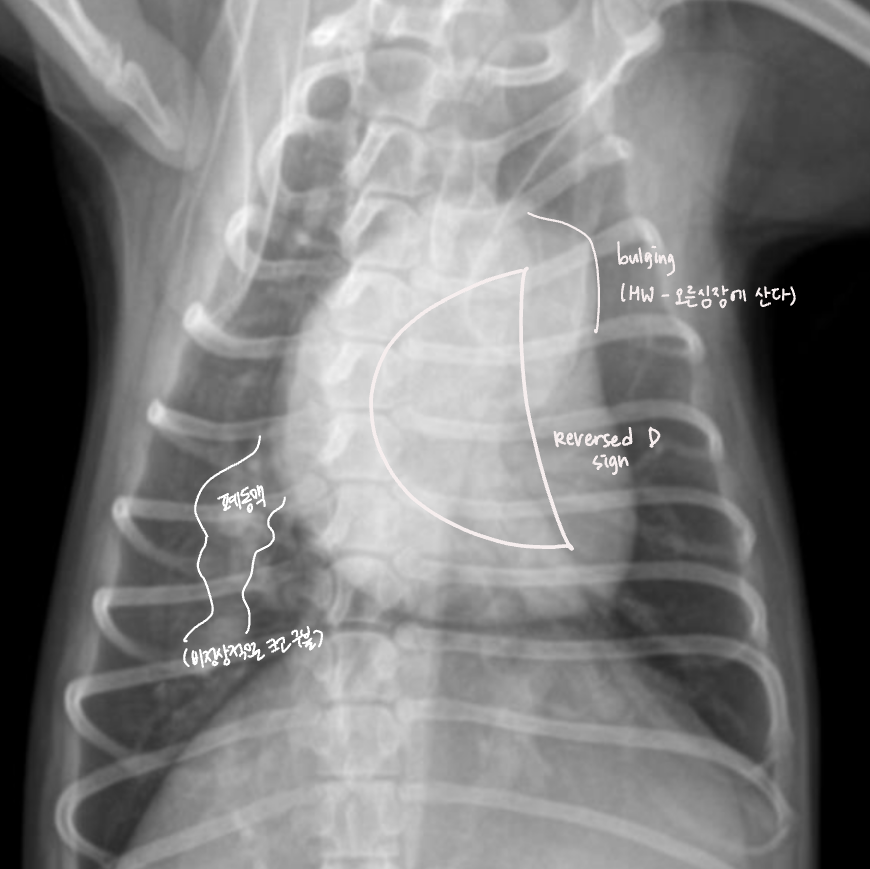

✳️ Vascular pattern

혈관이 커져서 폐가 지저분해 보이는 모양

1) Pulmonary hypertention - HW infection (심장사상충)